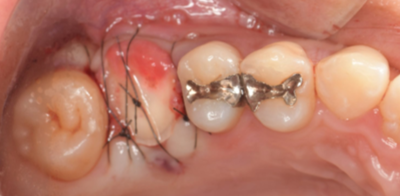

初診時口腔内写真

初診時パノラマX線写真と口腔内写真。

右上6に腫脹と排膿がみられた。